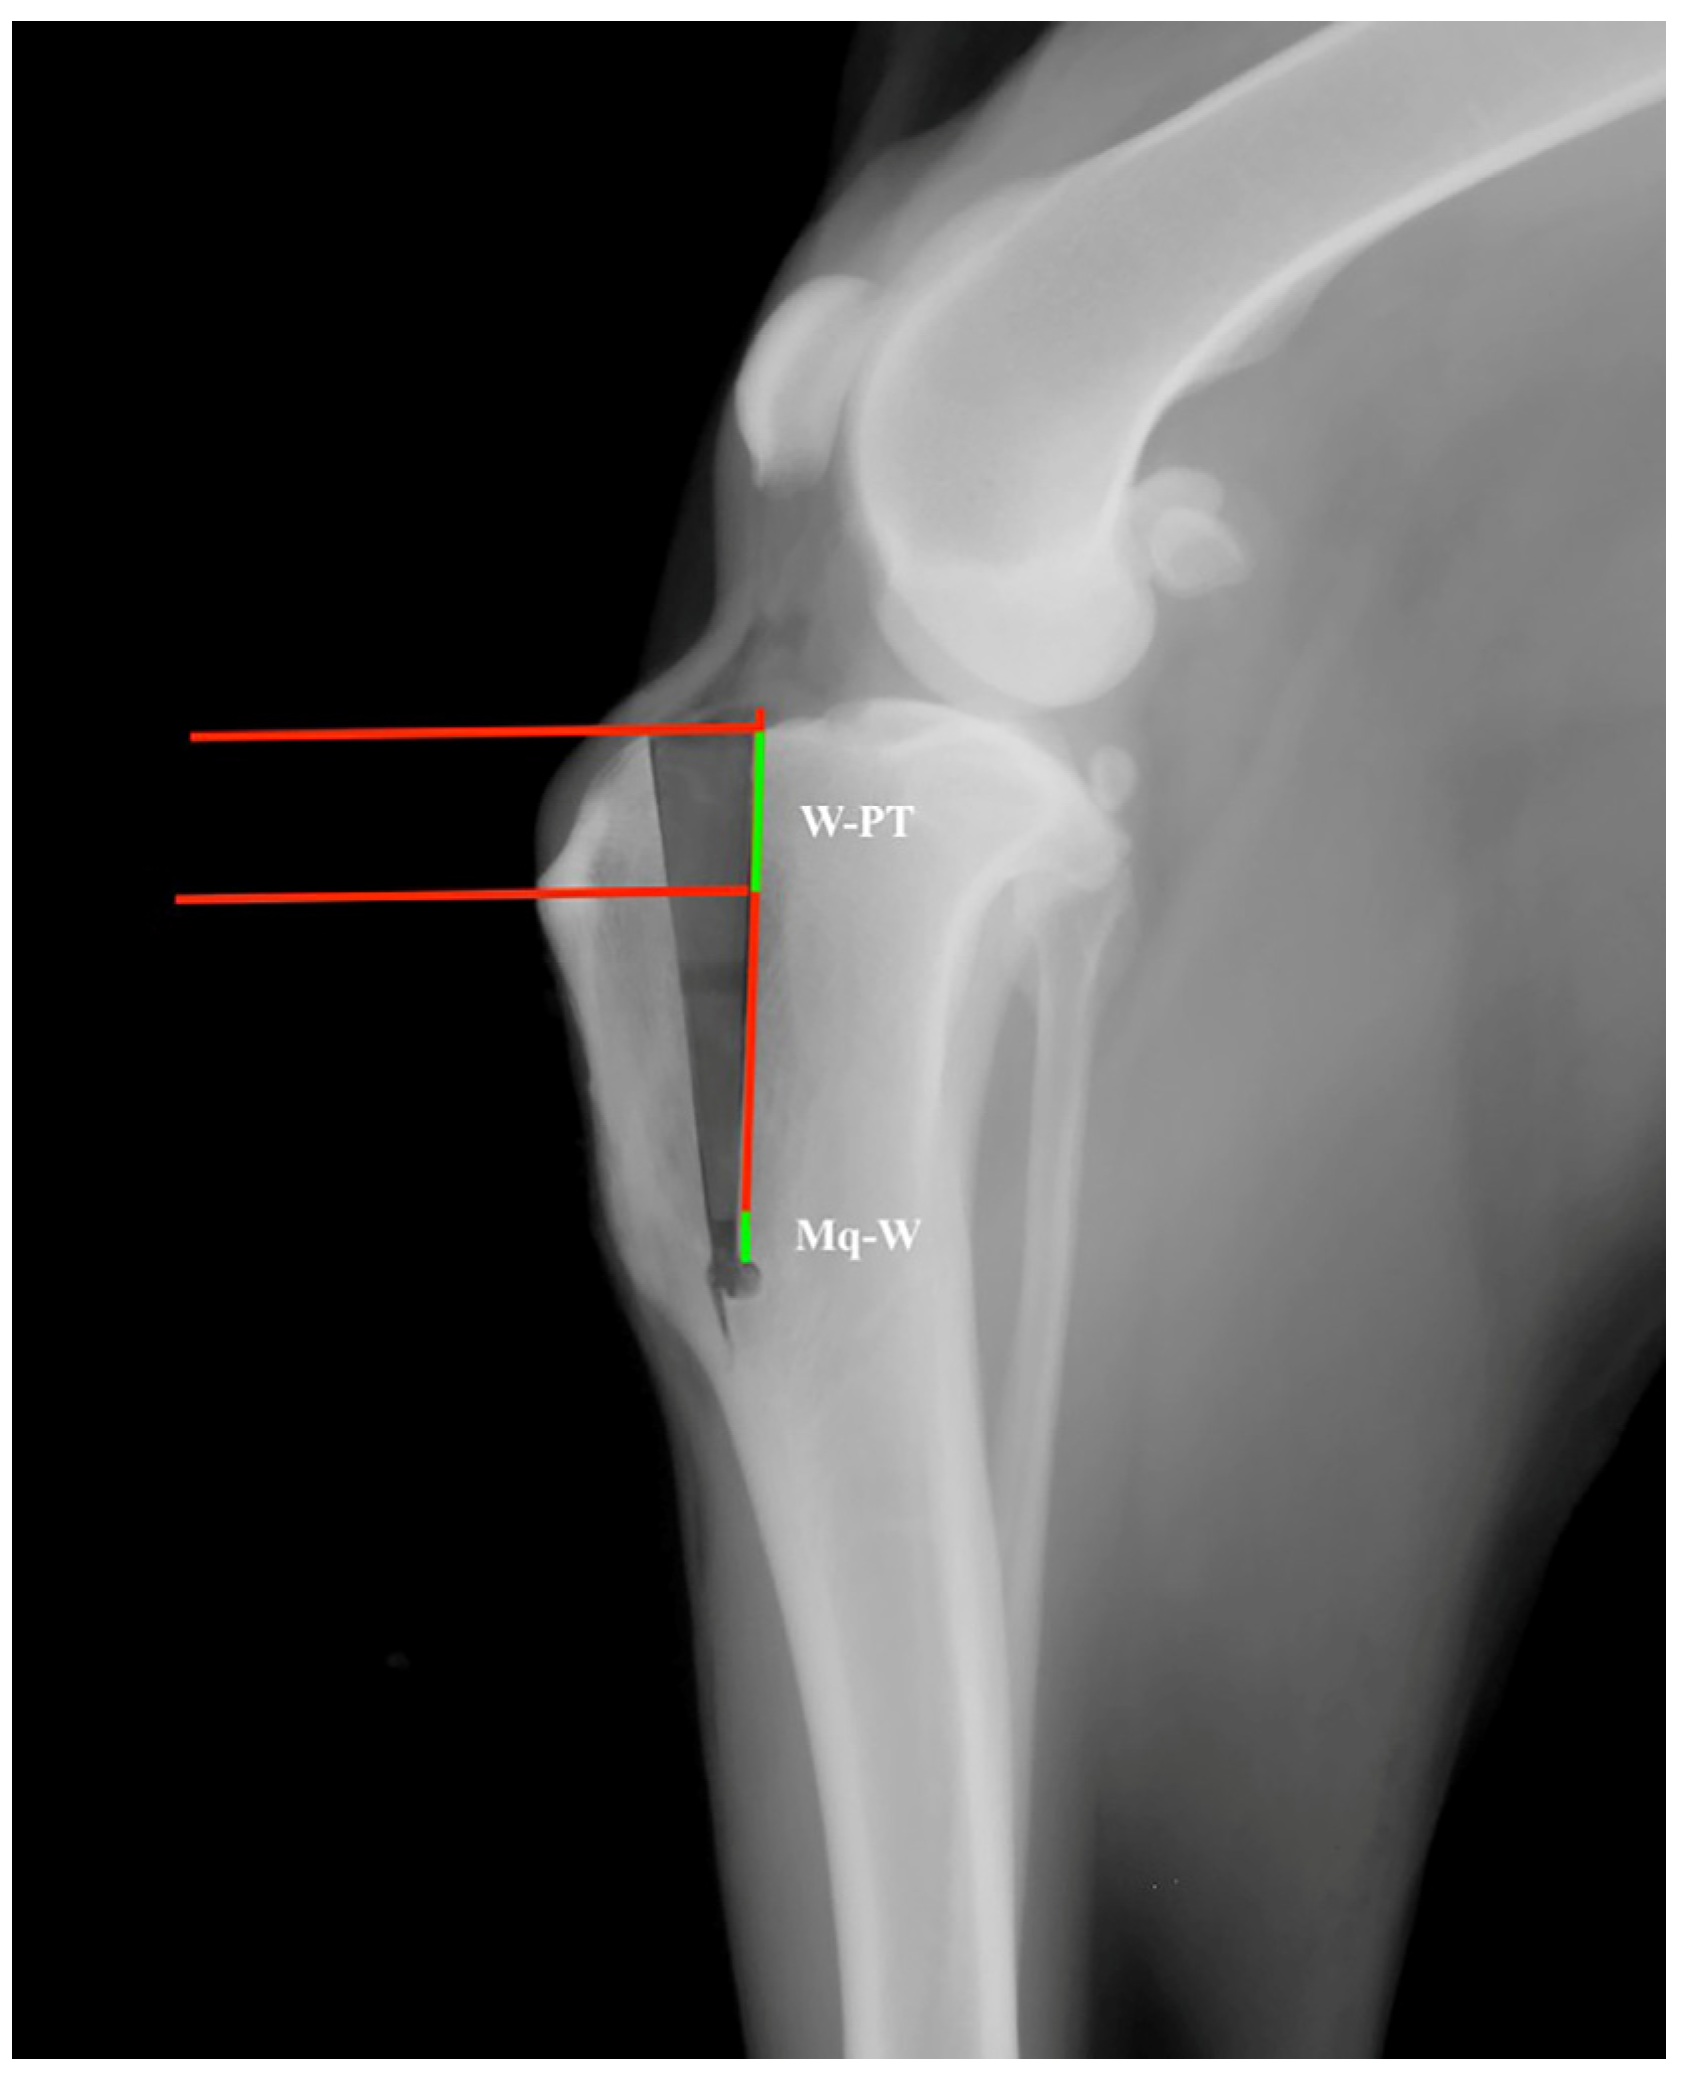

- For CT, first, the observer drew two circles representing the femoral and tibial condyles, marking the center. Next, he connected the two centers with a line and drew a line perpendicular to it, defined as the common tangent. The angle between the common tangent and the line drawn from the caudal margin of the patella to its insertion on the tibial tuberosity corresponded to the PTA. To measure the amount of advancement required, the observer considered the distance between the tibial tuberosity and the line perpendicular to the common tangent starting from the cranial margin of the patella [35] (Figure 1).

- For TAM, the tibial functional axis of the tibia, defined by a line joining the midpoint between the intercondylar tibial tubercles (in the stifle joint) with the center of the talocrural joint, was drawn. Then, the tibial plateau, defined by a line joining the points at the cranial-most and caudal-most edges of the medial tibial condyle, was drawn. Secondly, from the functional axis, a caudally directed 135° angle towards the femur was made. Next, a parallel line through the patellar insertion point on the tibial tuberosity was located. This line intersected the tibial plateau line that was previously drawn. A perpendicular line to the tibial plateau was placed starting from patellar insertion. Next, a parallel line through the intersection point was drawn. The distance between this line and the most-cranial point of the tibial tuberosity, measured along a line perpendicular to the function axis, was recorded as the required advancement [22] (Figure 2).